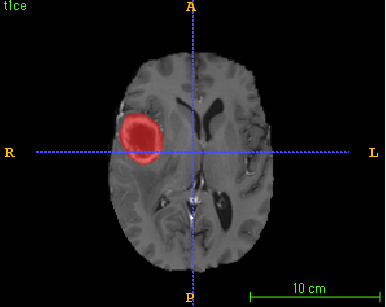

Post-contrast T1-weighted MR image로부터 자동으로 tumor segmentation할 수 있는 알고리즘

1)HGG(high grade glioma) brain tumor 환자의 post-contrast T1-weighted MR image로 부터 Tumor 영역을 자동으로 segmentation할 수 있다.

2)Segmentation 결과는 necrotic tumor core와 gd-enhancing tumor의 영역을 포함한다.